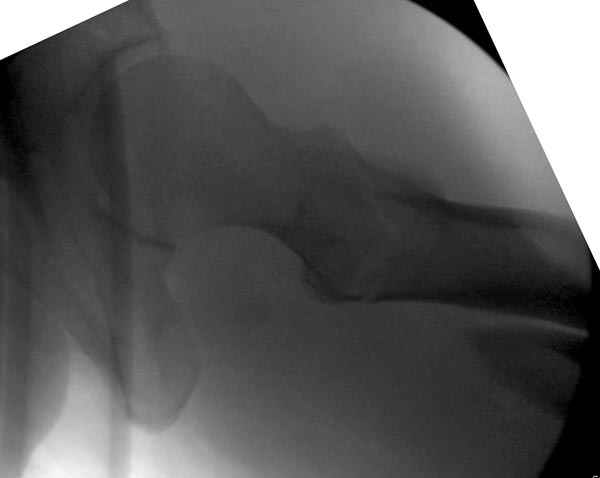

Как раз недавно у меня был примерный случай: больному 36 лет, поступил ночью, травма в результате мотоциклетной аварии, кроме чрезвертельного и спирального перелома левого бедра имеется переломы костей предплечья с этой же стороны. Скелетное вытяжение, а на следующий день больной про оперирован на ортопедическом столе с дистракцией. Чтобы не расколоть чрезвертельный перелом провели временную спицу ближе к переднему кортексу, из малого разреза костодержатель для репозиции, а фиксацию провели антиградным штифтом. Этапы операции на снимках.

Да, сейчас это и у нас самый напрашивающийся выбор. Сделали гвоздем ChM, картинки в приложении.